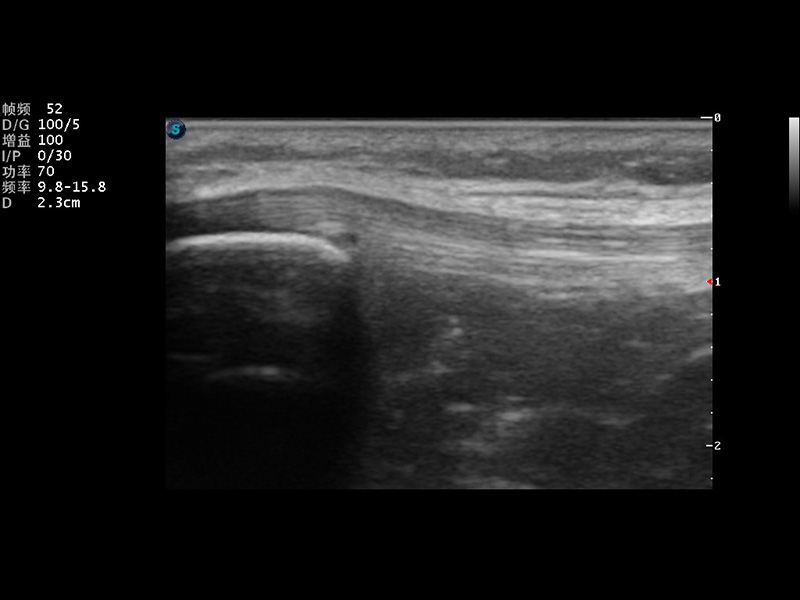

S9便携式彩色多普勒超声诊断仪是狗万官方网站研发的高端便携彩超设备,外观设计新颖、产品性能卓越。S9在便携超声领域采用了突破传统的触摸屏交互设计,并以先进的软件硬件技术和设计理念,为您带来清晰的图像质量、稳定的工作性能和便捷的操作体验。